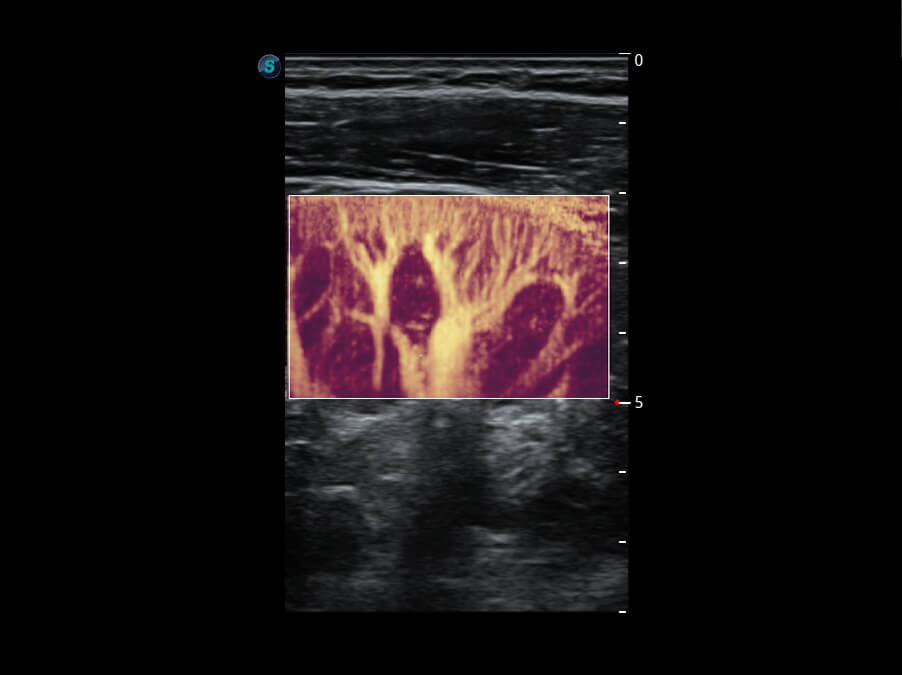

S60探头工艺,从前端信号处理每一个环节采集无损声学数据,真实还原组织原貌,再现解剖细节。

• 新型复合材料探头( 12L-A )